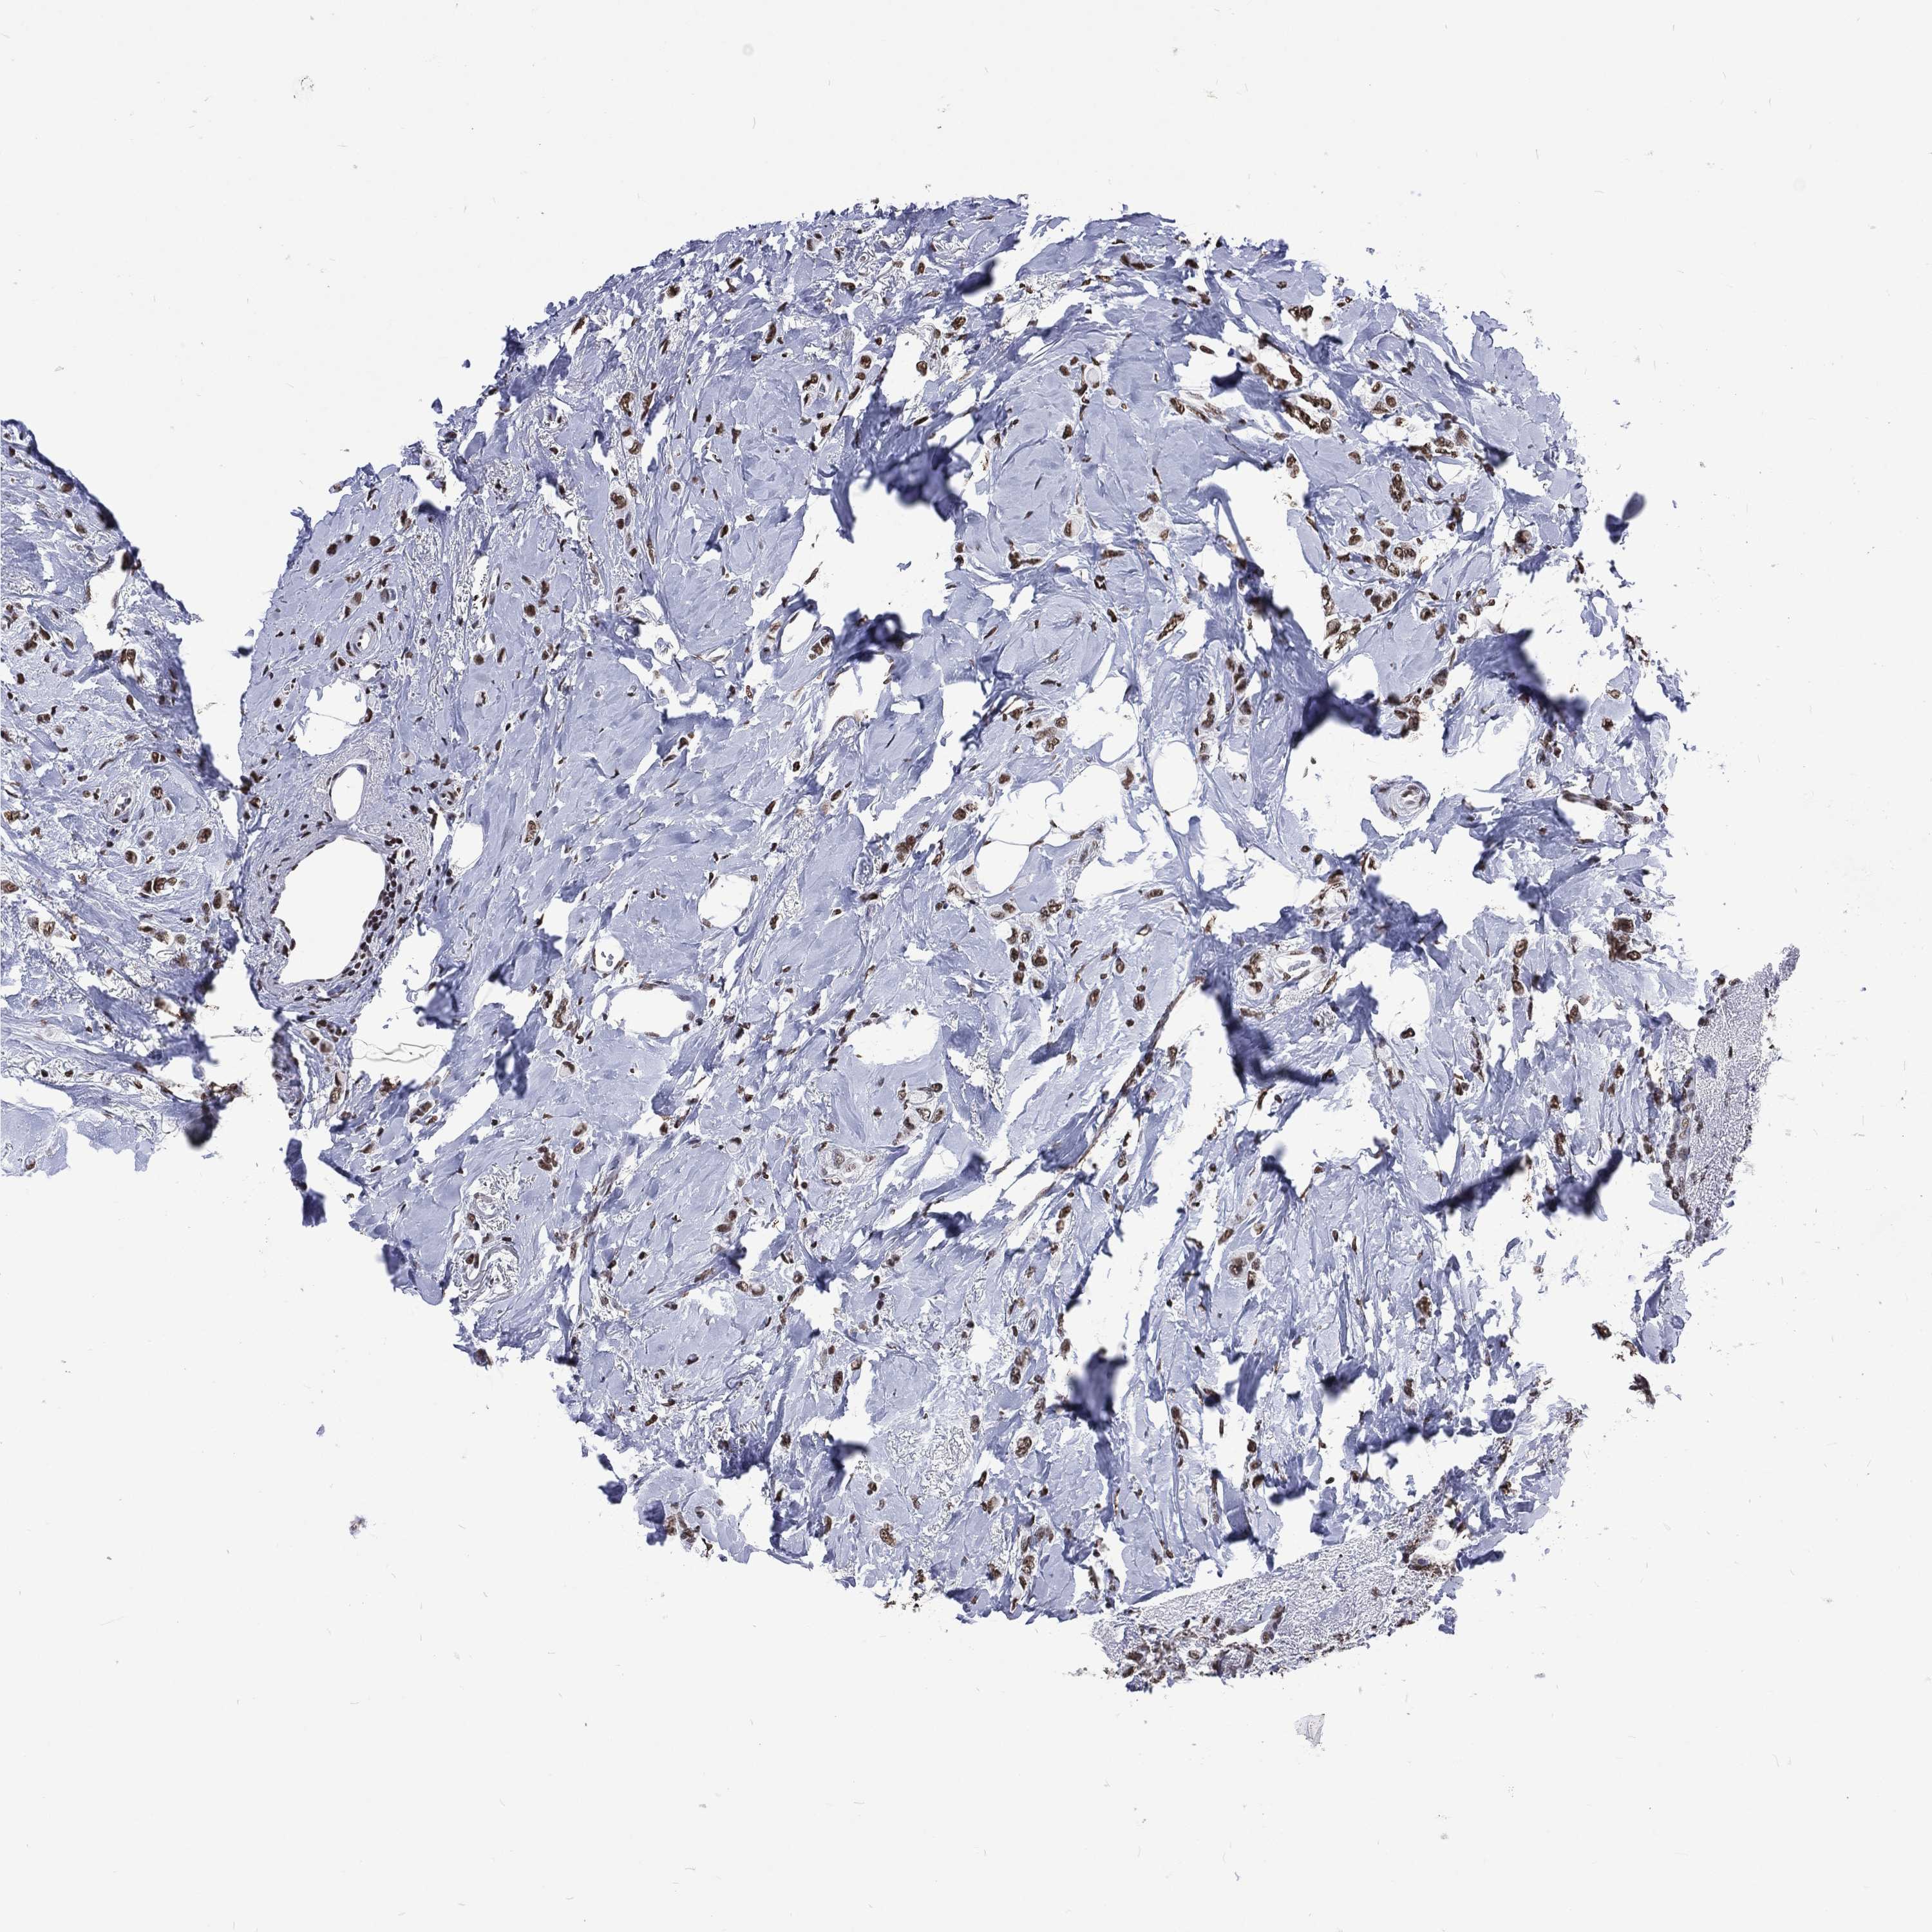

CANCER BREAST CANCER Show tissue menu

BRCA TCGA BRCA VALIDATION PROTEIN EXPRESSION

RETREG2 is potential prognostic, high expression is unfavorable in Breast Invasive Carcinoma (TCGA)